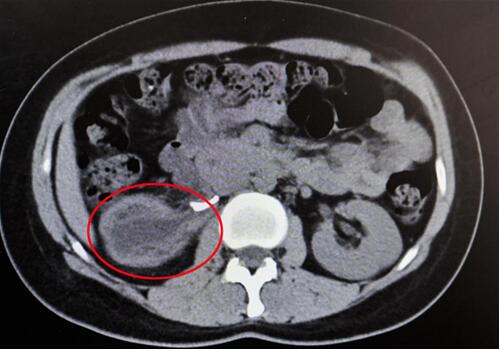

紅圈部分為手術(shù)前腎積水情況。院方供圖

“腎臟就像是一個皮球,因輸尿管完全閉鎖,里面的積水無法排出、越積越多,已經(jīng)把表皮撐得很薄,在造影下甚至都看不清邊緣了!苯纳魅握f,“由于之前手術(shù)的粘連嚴重,手術(shù)難度頗大,腎臟能否保住是個未知數(shù)。”